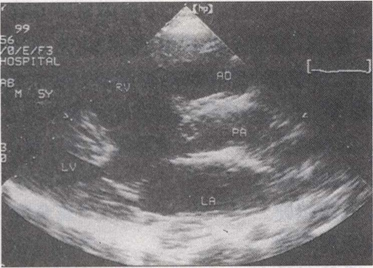

25.该病例最可能的诊断()